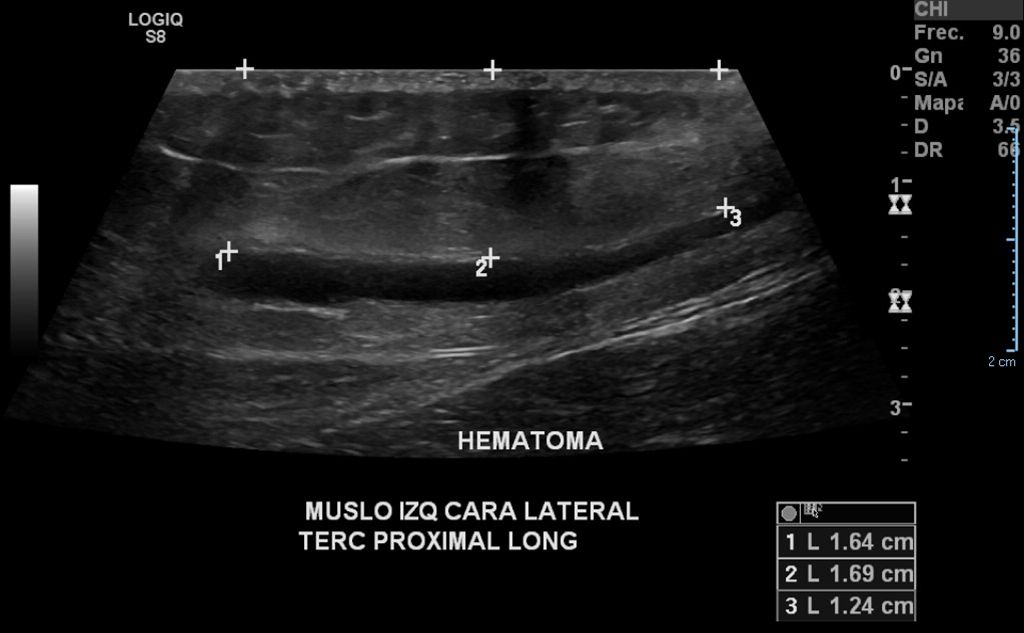

• Paciente refiere fuerte golpe hace 2 semanas, con posterior aumento de volumen en cara lateral del muslo a nivel del tercio proximal.

• Diagnóstico: Hematoma encapsulado

En región de aumento de volumen, se observa un aumento de la ecogenicidad del tejido celular subcutáneo, con edema asociado, con múltiples áreas de necrosis grasa y con hematoma subcutáneo que no contacta con la fascia muscular

Hallazgos: Piel de apariencia conservada. En el espesor del tejido celular subcutáneo de la zona de aumento de volumen se aprecia lesión nodular, ovoidea, alargada, hipoecogénica, bien delimitada, sin señal al Doppler color, con aumento de al ecogenicidad del tejido adiposo circundante, que mide 5 x 3 x 0. 4 cm. Aproximadamente. Se aprecian pequeños focos redondeos hipoecoicos, redondeados, el mayor miden hasta 3 mm.

Planos musculares de aspecto ecográfico habitual.